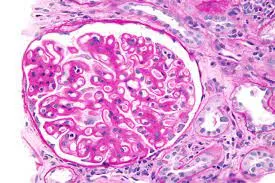

Hiperlipidemia na Nefropatia Membranosa: Um novo olhar que impacta no tratamento

A dislipidemia na Nefropatia Membranosa sempre foi tratada como dano colateral da síndrome nefrótica. Essa revisão muda a pergunta — e muda o que fazemos com ela.